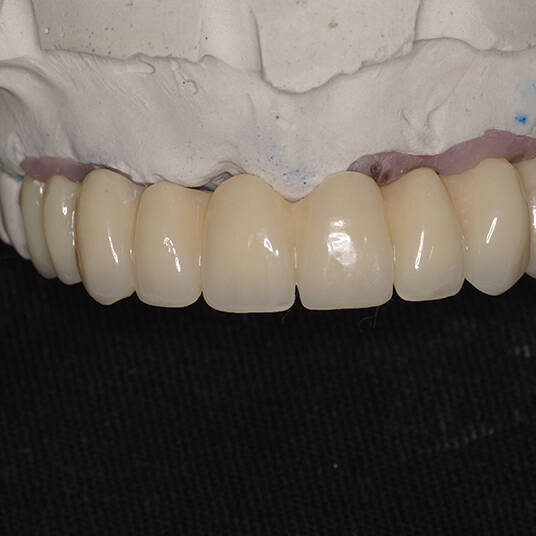

Utilizamos a tecnologia CAD CAM, um sistema avançado que possibilita a confecção precisa das próteses dentárias diretamente sobre os implantes. Esse método inovador garante um ajuste perfeito, um resultado estético superior e proporciona muito mais conforto e durabilidade. Com o CAD CAM, nossos pacientes contam com um processo mais rápido e previsível para alcançar o sorriso desejado.